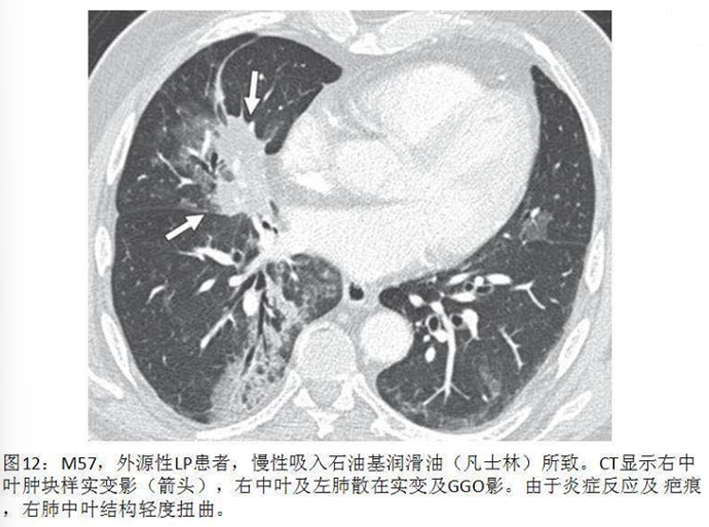

脂质性肺炎被认为由肺泡内含脂物质异物反应所致,脂质到达肺泡的机制:摄入(非挥发烃类)或吸入(挥发烃类),少数矿物油如汽油,即使经静脉注射也可导致肺损伤。在肺泡内,油脂乳化后被巨噬细胞吞噬,肺泡巨噬细胞不能代谢脂肪物质,当巨噬细胞死亡后油脂反复进入肺泡;油脂异常释放导致巨噬细胞肉芽肿反应、慢性炎症反应、肺泡及间隔纤维化;新鲜病灶显示肺泡被载脂巨噬细胞浸润,肺泡壁和间隔基本正常;进展性病灶显示巨大的空泡和肺泡壁、支气管壁和间隔炎性浸润,大量含脂空泡周围纤维化和实质破坏是晚期病变的特征。如果吸入矿物油或植物油,不易在体内分解,易在体内形成结节或肿块。如果吸入动物油,在体内可被分解为脂肪酸,导致炎症反应,局部肺水肿或肺出血。临床表现缺乏特异性,个体差异明显,从无症状到严重,甚至危及生命,常因患者年龄、吸入脂质的时间、数量及种类而不同。有症状的外源性脂质性肺炎常表现为慢性咳嗽或呼吸困难,其他表现为胸痛、咯血、间歇发热等。查体可发现叩诊浊音,听诊可闻及爆破音或干啰音。在长期持续进展性疾病患者中,体检可发现慢性缺氧,如杵状指。外源性类脂性肺炎可模拟许多其他肺部疾病,包括癌、肺炎、急性呼吸窘迫综合征和局部肉芽肿,HRCT最常见的表现是气腔实变、磨玻璃影、铺路石征、小叶间隔增厚、肿块样病变。急性外源性脂质性肺炎一般在吸入后半小时内出现肺部影像异常,大部分患者在24小时内出现肺部阴影,通常呈磨玻璃或实变影,一般在2周至8个月可逐渐改善或吸收,偶尔会遗留少许瘢痕纤维。慢性外源性脂质性肺炎最常见的影像学表现为一个或多个肺段的磨玻璃结节或实变影,通常在支气管周围分布,累及下叶最常见。实变可伴临近肺组织扭曲,在疾病晚期,由于油脂从肺泡内运送至肺间质,可出现增厚的小叶间隔或纤维化,还可见到铺路石征,也可表现为含脂质的结节或肿块影,由于慢性炎症及纤维化,肿块边界常不规则或有毛刺。下图为文献报道的一例急性外源性脂质性肺炎,患者胸部CT主要表现为实变,其中有液化坏死灶。下图为3例外源性脂质性肺炎患者的胸部CT,主要表现为肺结节/肿块和磨玻璃影。治疗3个月后,病变较轻者明显吸收。外源性脂质性肺炎的诊断主要基于暴露史,与疾病相符的影像学改变,唾液、支气管肺泡灌洗液或活检肺组织病理发现富含脂质的巨噬细胞,需要综合以上考虑诊断。支气管肺泡灌洗液的外观有提示价值,常为白色或浑浊液体,在表面可见脂肪漂浮层。